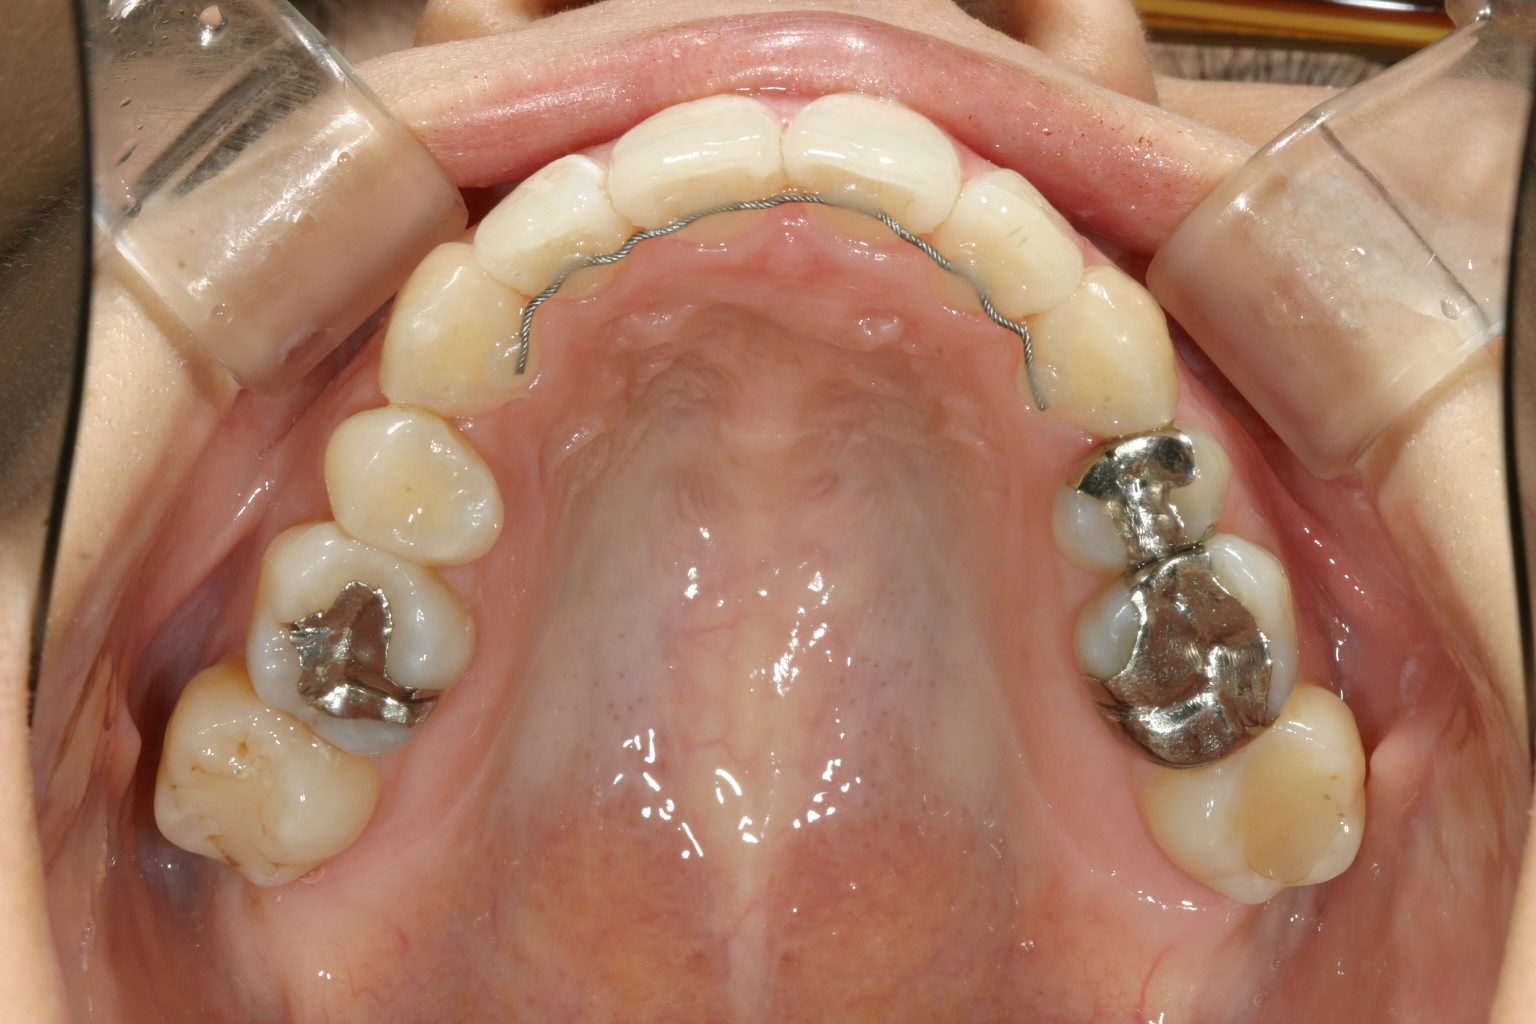

前歯のアーチの尖りを丸く仕上げました。

特に上顎のアーチが狭くなり先が尖って、それに合わせて下顎も叢生が再発していました。